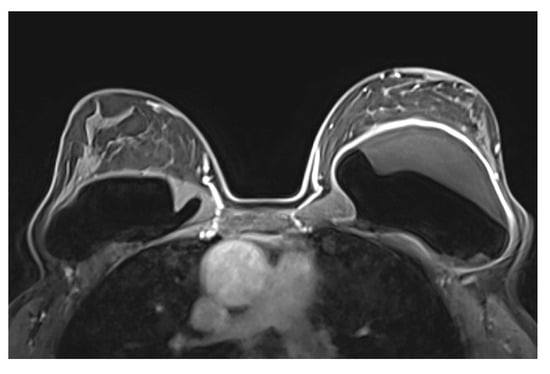

5.2.5. Implant Rupture

| Rupture * | Implant shell | Intact fibrous capsule | Intracapsular |

| Implant shell and fibrous capsule | Extracapsular | ||

| Definitive rupture | Linguini sign | Low signal lines within the silicone |

| Subcapsular lines | Low signal lines parallel to the capsule surrounded by silicone | |

| Free Silicone | Extracapsular silicone | |